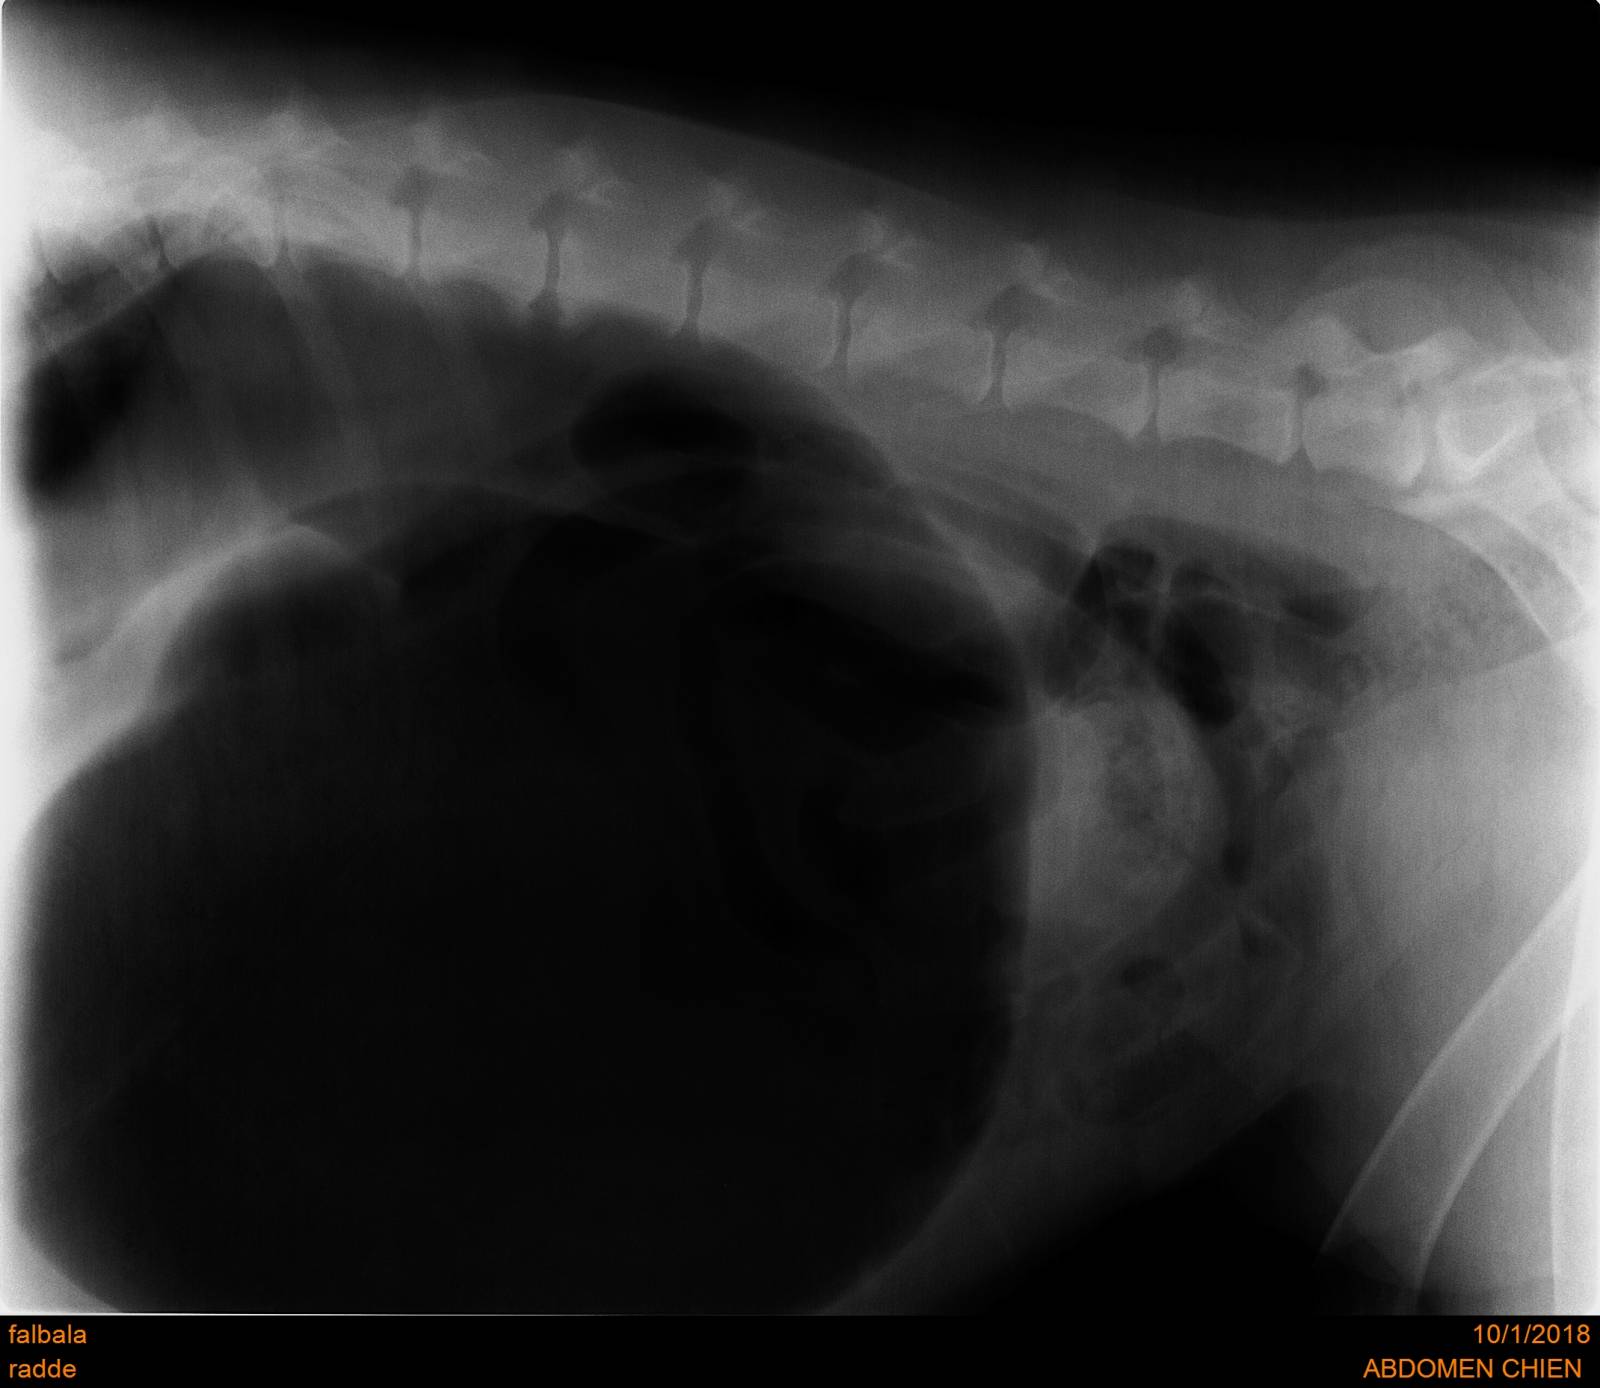

Le Syndrome Torsion Dilatation d'Estomac

Le syndrome dilatation torsion d'estomac est une pathologie très sérieuse et fatale si elle n'est pas traitée en urgence très sérieusement.

Les signes cliniques : tentatives de vomissements, agitation pâleurs des muqueuses, gonflement du ventre, état de choc progressif rapide, et ceci sur des races prédisposées (souvent grands chiens au thorax profond : Dogue Allemand, Saint Bernard, Boxer, Labrador etc..)